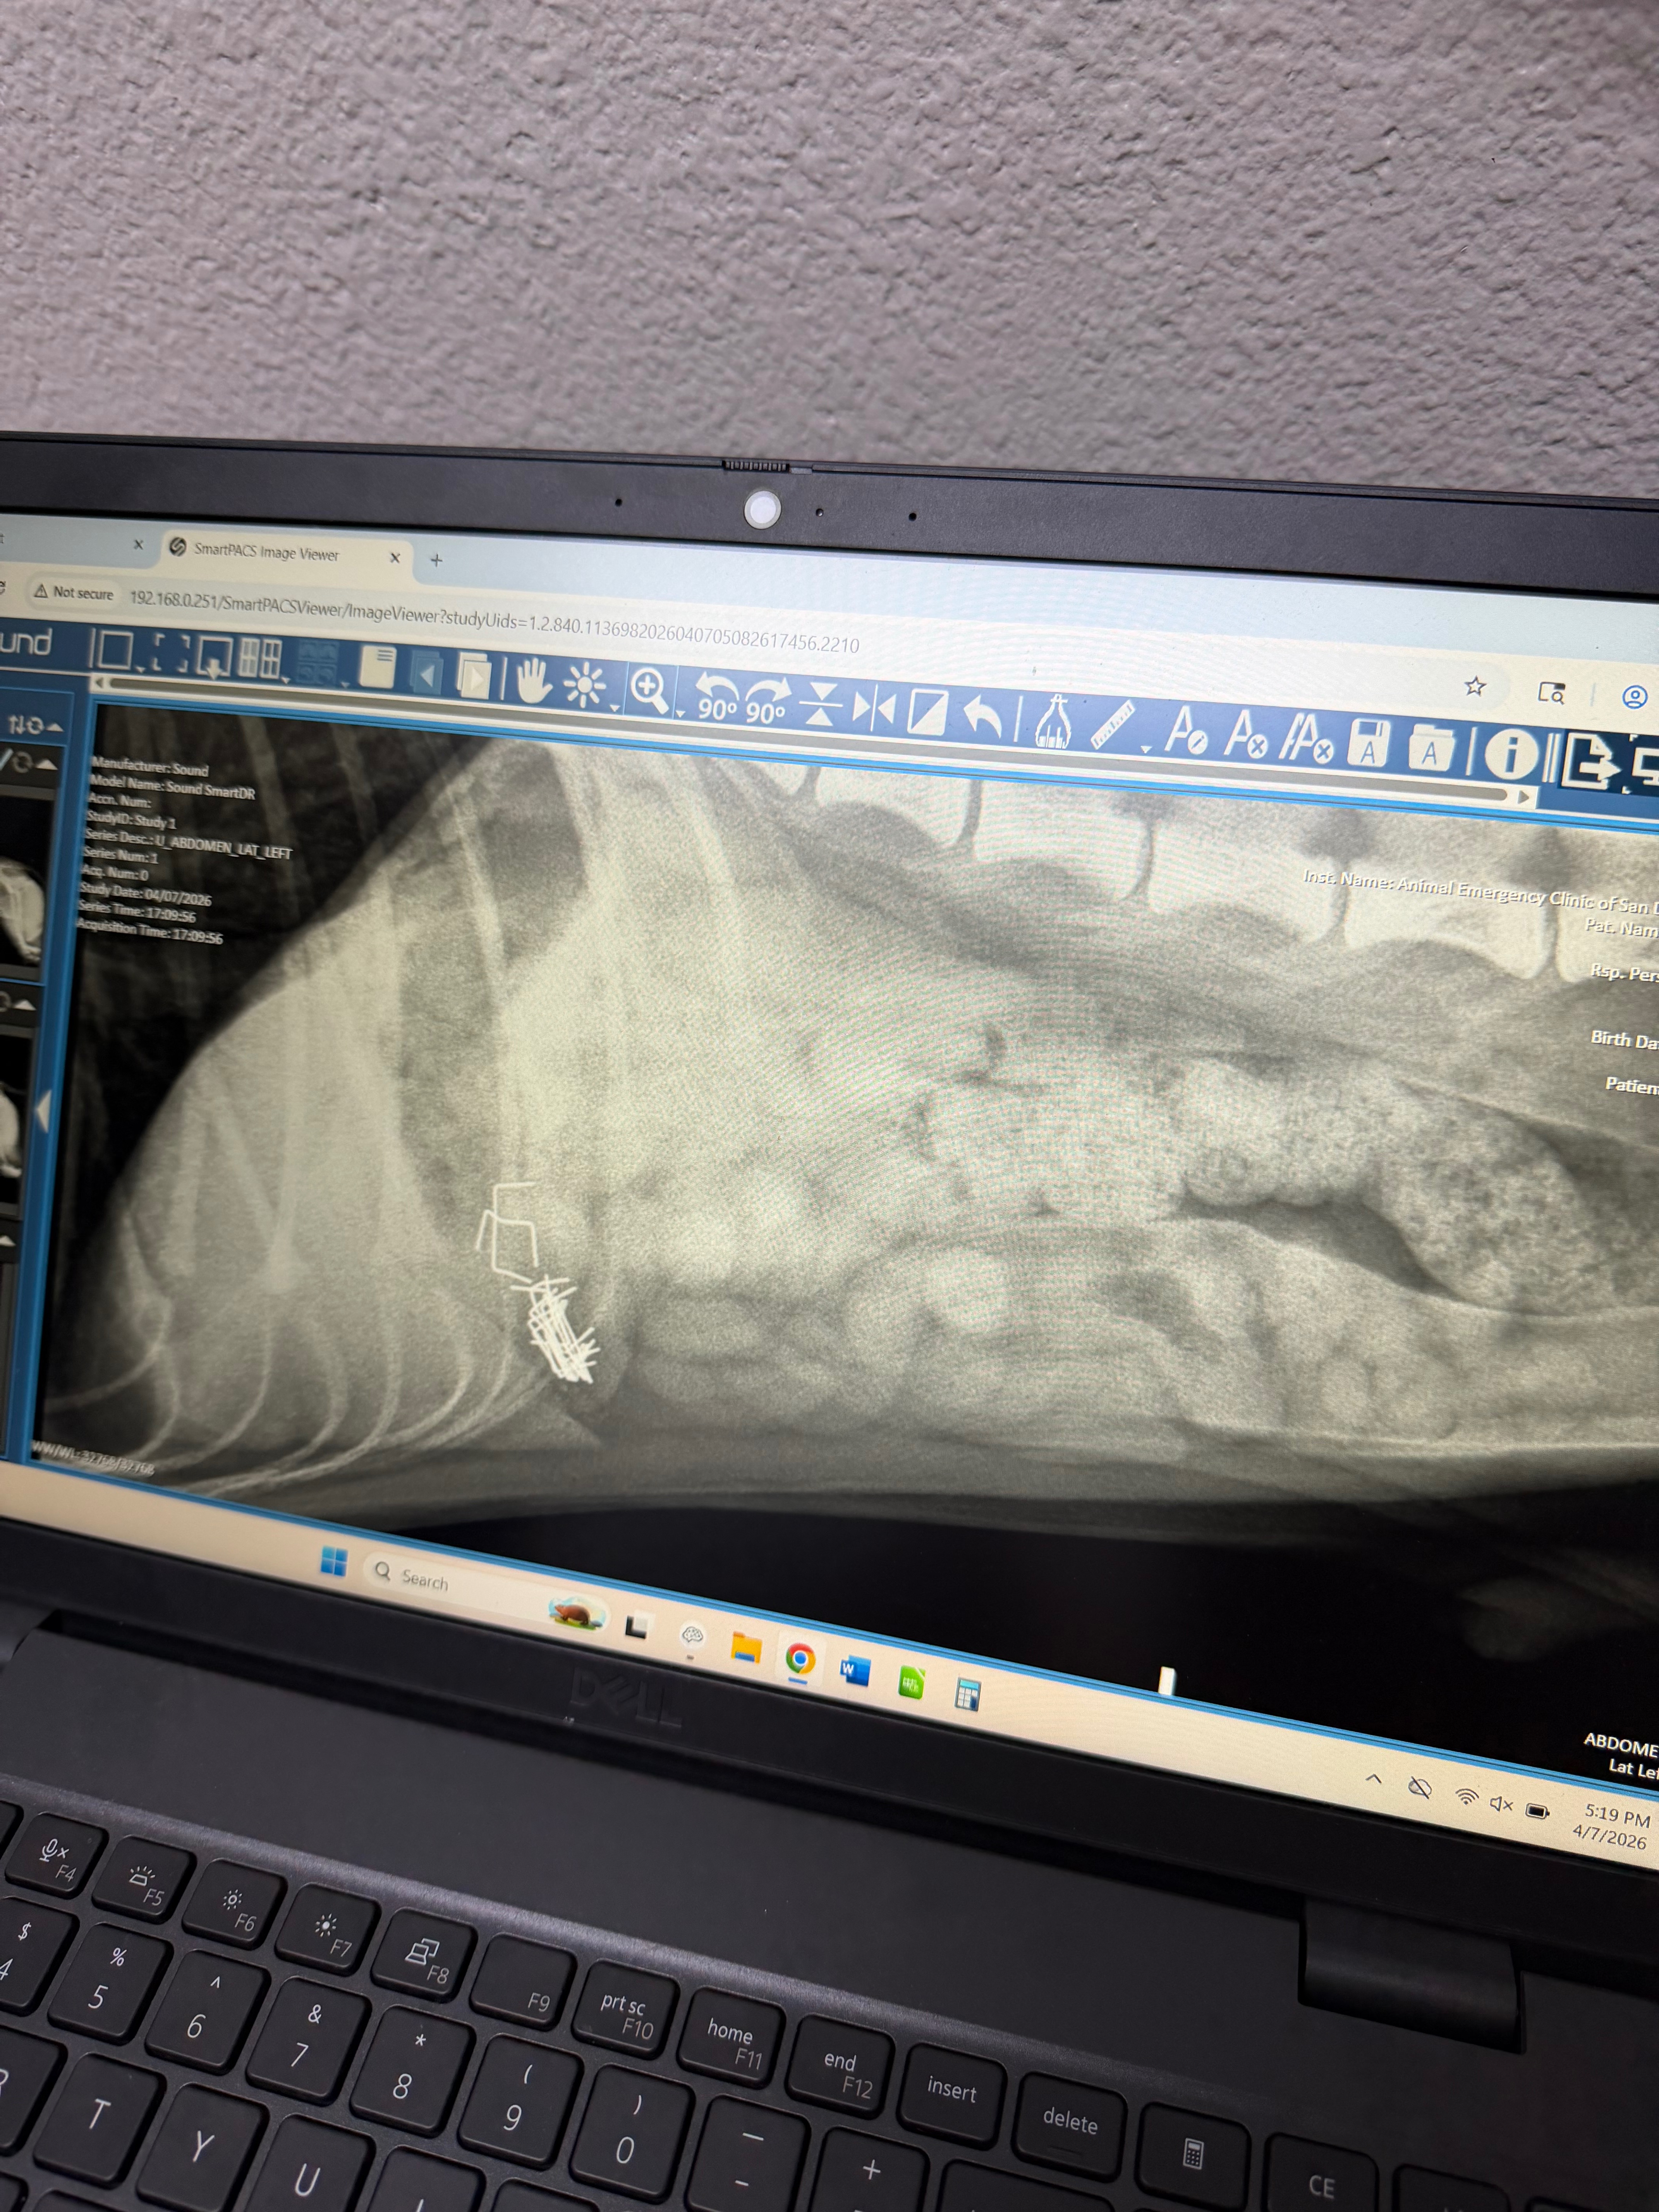

Tuesday, April 7th, my 9-month-old puppy got hold of a stapler and ingested a large number of staples.

They took X-rays and over 20 staples in his belly. They are performing surgery as quickly as they can because if he were to pass them or throw them up, it could be life-threatening.